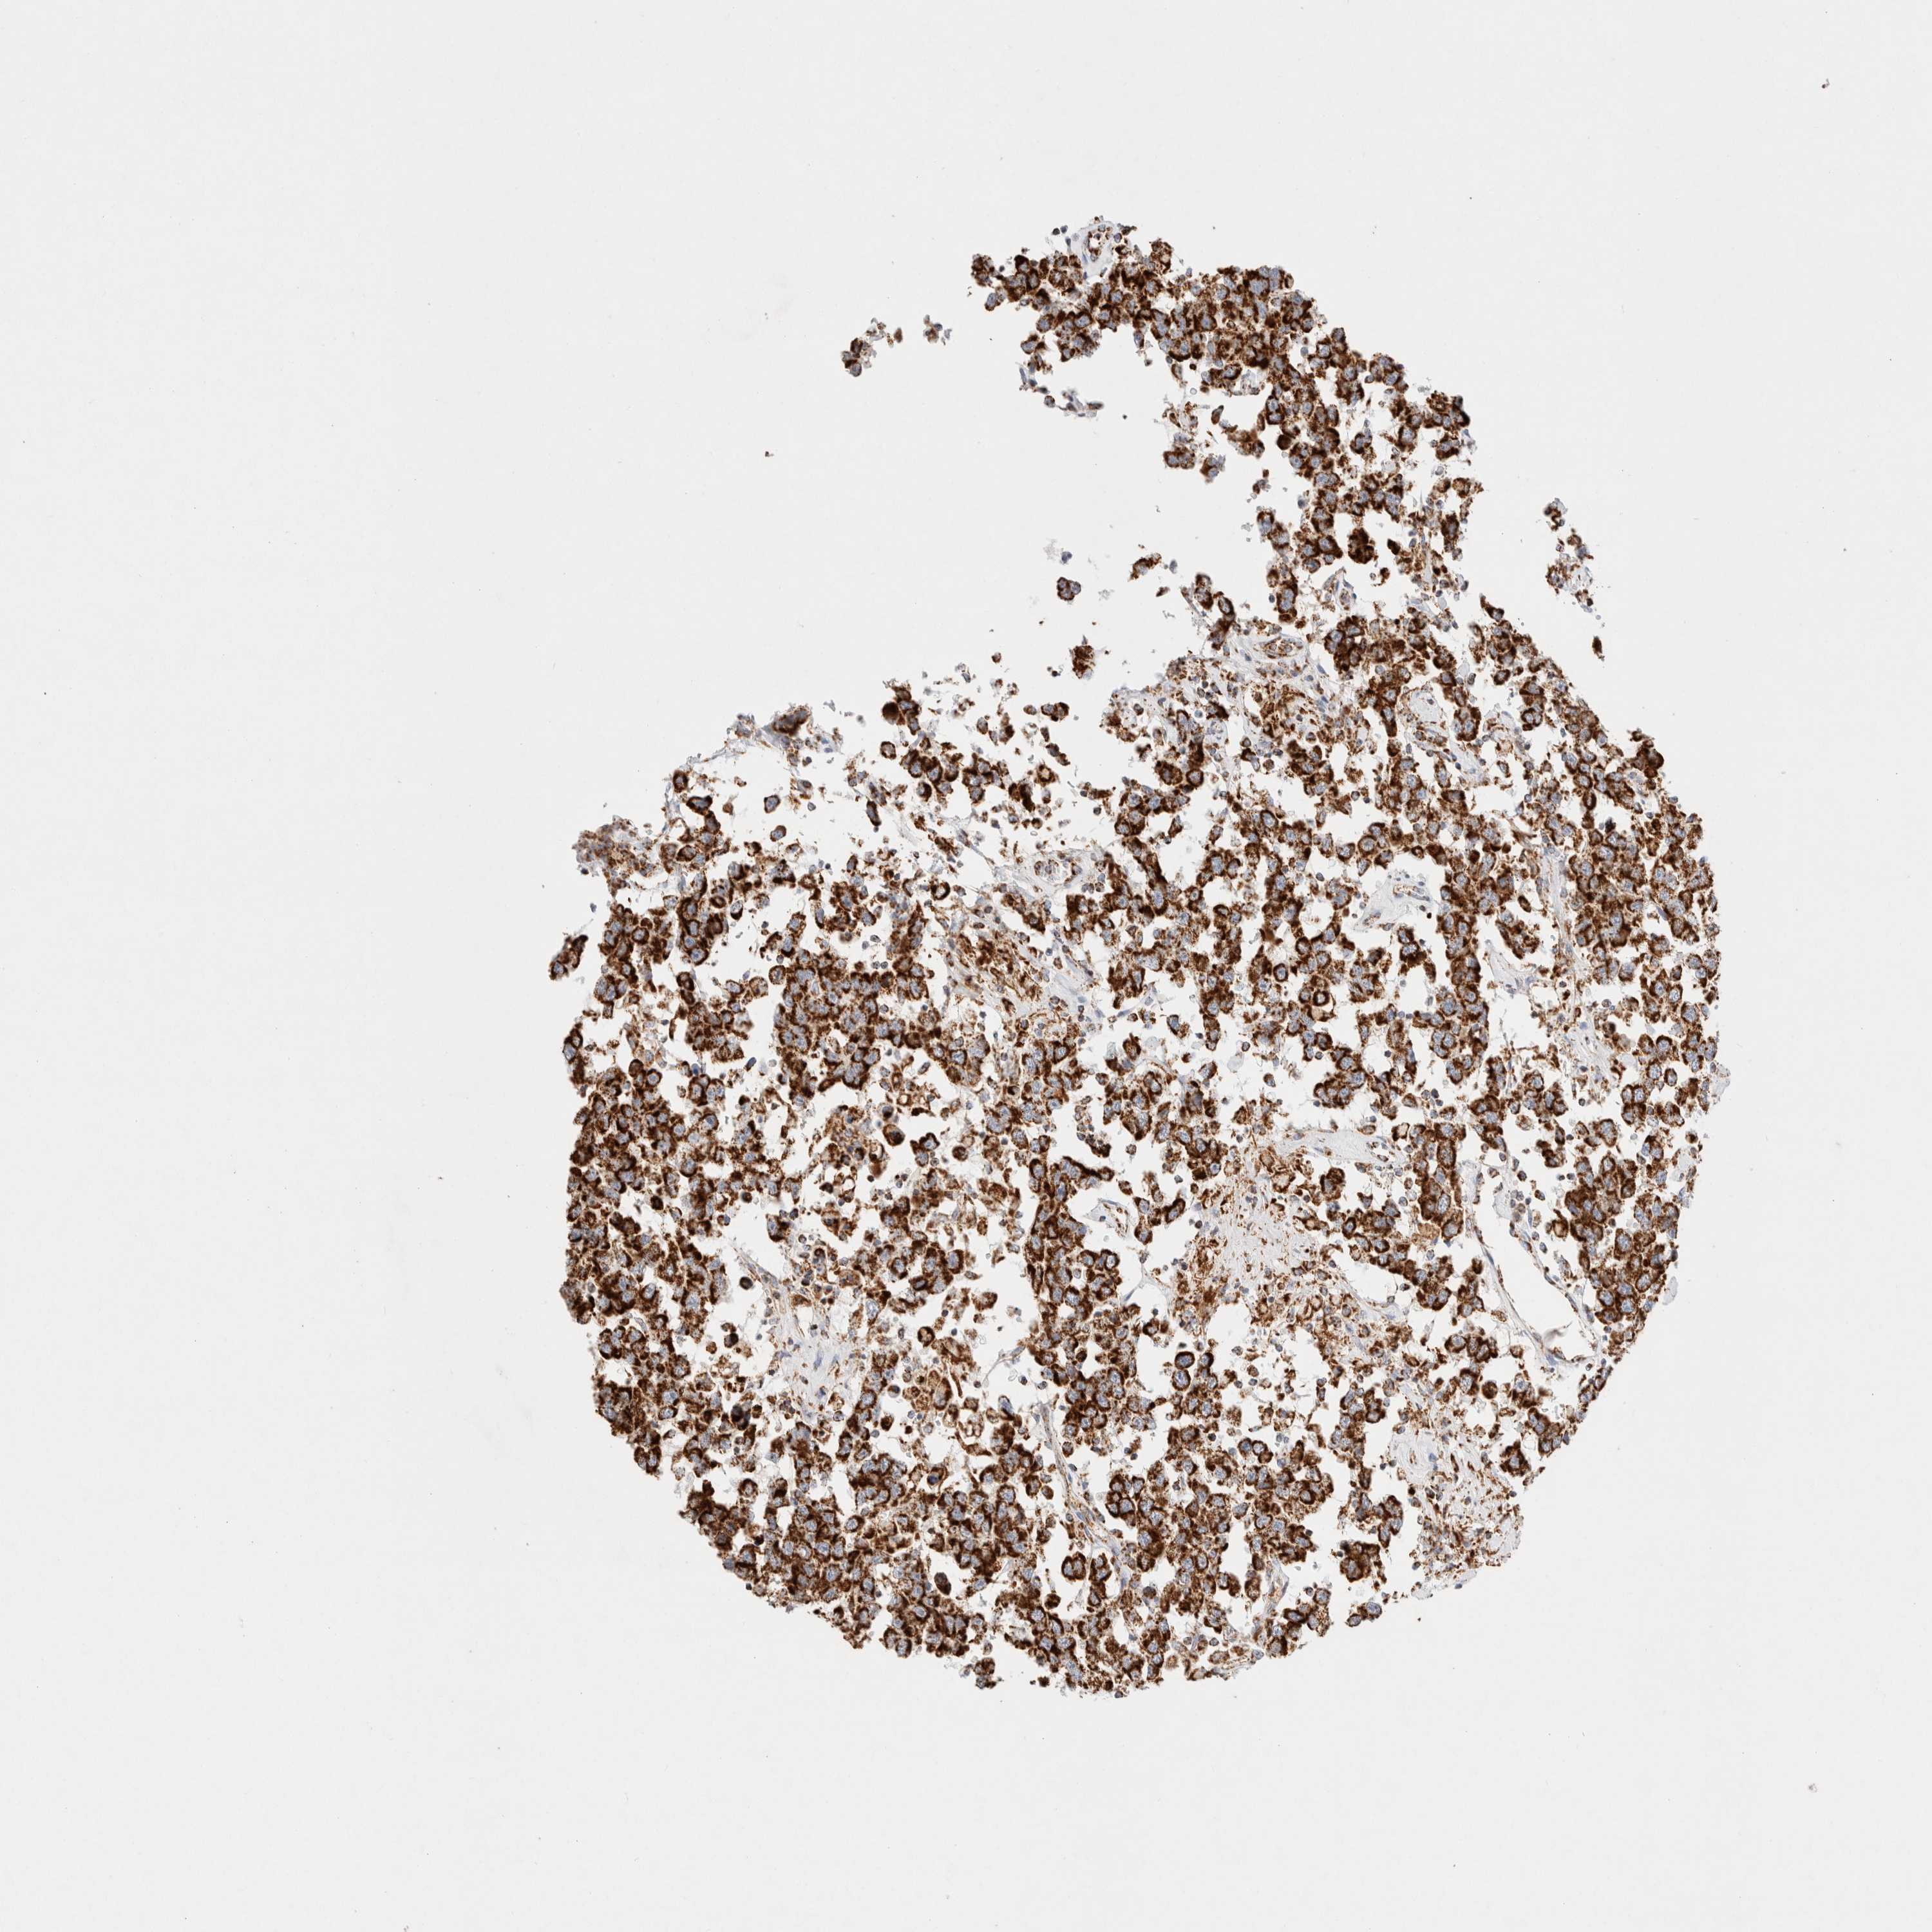

TESTIS CANCER - Protein expressioni

A mouse-over function shows sample information and annotation data. Click on an image to view it in a full screen mode. Samples can be filtered based on level of antibody staining by selecting one or several of the following categories: high, medium, low and not detected. The assay and annotation is described here.

Note that samples used for immunohistochemistry by the Human Protein Atlas do not correspond to samples in the TCGA dataset.

Antibody stainingi

Antibody staining in the annotated cell types in the current human tissue is reported as not detected, low, medium, or high, based on conventional immunohistochemistry profiling in selected tissues. This score is based on the combination of the staining intensity and fraction of stained cells.

Each image is clickable and will lead to virtual microscopy that enables deeper exploration of all samples and also displays staining intensity scores, fraction scores and subcellular localization as well as patient and tissue information for each sample.

Antibody HPA039874

Antibody CAB014889

Antibody CAB026335

Carcinoma, Embryonal, NOS

Seminoma, NOS